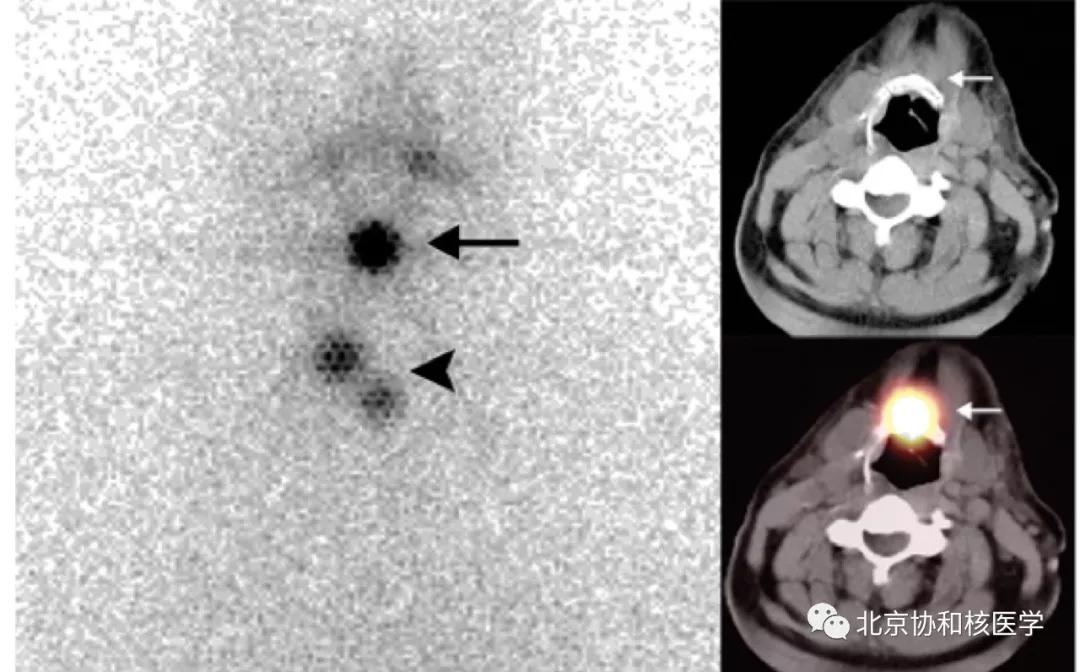

63岁女性,甲状腺乳头状癌甲状腺全切除术后,碘131治疗后,除颈部残余甲状腺外,碘扫见右侧腮腺软组织密度结节,摄取明显增高,穿刺活检提示腮腺良性肿瘤[2]: